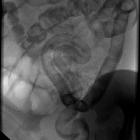

Fluoroscopy: contrast enema

Contrast enema may demonstrate a small caliber to the left colon with multiple filling defects within due to retained meconium. The rectum is usually normal in size, unlike Hirschsprung disease. The use of high osmolar ionic contrast media for enema in a neonate or infant is controversial due to the risks associated with fluid shift . The enema can be both diagnostic as well as therapeutic and is usually accompanied by the passage of meconium during or after the procedure.